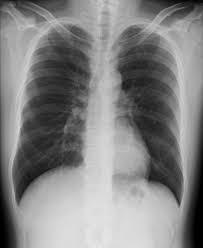

よって高齢者に多い誤嚥性肺炎、圧迫骨折、大腿骨頸部骨折などの診断に移動せずに撮影が行えます。

在宅、施設の患者様のX線撮影 胸部・腹部など内科領域から腰椎や膝関節などの整形領域まで、全身のレントゲン撮影を可能としています。